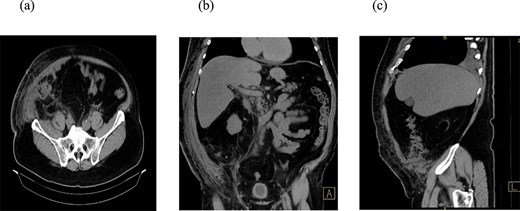

A 66-year-old patient was admitted to the Clinic for Digestive Surgery as an emergency case with a history of open appendectomy nine days earlier, operated on in another institution, with a classical appendectomy performed through a McBurney muscle-splitting incision. Upon admission, fecal content was observed in the area of the operative wound, raising suspicion of a colo-cutaneous fistula. On physical examination, the abdomen was soft and non-tender, without signs of peritoneal irritation. Fecal discharge was present at the site of the previous surgical incision. The patient was initially managed conservatively with dual antibiotic therapy, analgesics, antithrombotic medication, fluid and electrolyte replacement, wound care, and gastroprotective therapy. A collection device was applied to the wound, and the amount of fecal output was monitored. The patient had a high-output colo-cutaneous fistula, with daily drainage ranging from 600 to 1000 ml. Due to the failure of conservative management and the persistence of high-volume output, surgical intervention was indicated. Laboratory tests revealed mild electrolyte disturbances, leukocytosis (14.9 × 109/L), and a C-reactive protein level of 86.3 mg/L. Imaging techniques, computed tomography (CT) scan of the abdomen (Fig. 1), demonstrated a collision of the cecum with the anterior abdominal wall at the site of the previous laparotomy incision, accompanied by surrounding mesenteric stranding. In the region of the anterior abdominal wall, fat stranding was found within the subcutaneous tissue, indicating inflammation, as well as air inclusions originating from the cecum, findings consistent with a colo-cutaneous fistula.

CT scan of the abdomen. Three reconstructions were evaluated: Axial (a), coronal (b), and sagittal (c). The findings suggest a collision of the cecum with the anterior abdominal wall at the site of the previous laparotomy incision, accompanied by surrounding mesenteric stranding. In the region of the anterior abdominal wall, there is fat stranding within the subcutaneous tissue, indicating inflammation, as well as air inclusions originating from the cecum, findings consistent with a colo-cutaneous fistula.